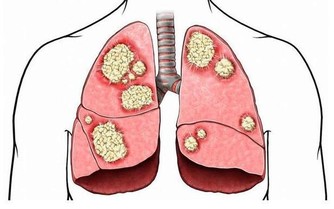

1.當心結腸癌盯上你憋便是不好的生活習慣,大便如果不及時排出,

水分就會被腸道反覆吸收,導致大便更加乾結難排。

大便中的毒素在體內積累時間過長,有害物質被腸道吸收,就會出現精神委靡不振、頭暈乏力、食慾減退等症狀,嚴重者甚至會引發腸道癌症。

3.容易造成便秘總有些場合,比如長途乘車上、上課考試途中,不能出去方便。「排便習慣不好,大便不規律,憋便都容易造成便秘,這和結腸癌等腫瘤的發生有相關性,但不是決定因素。所以大家也無需神經兮兮動不動就跑廁所,幾天排一次便不代表就吸收了大便中的毒素中毒了。」北京婦產醫院泌尿外科主任馬樂說。